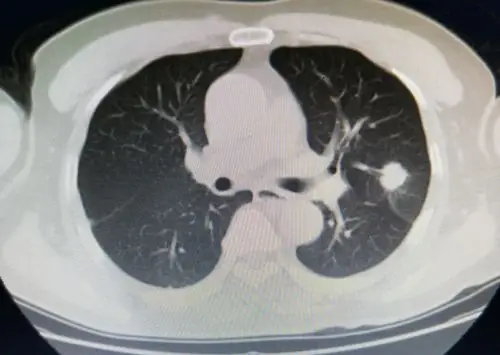

左上肺叶实性结节,不规则,可见毛刺,根据临床经验考虑为肺癌可能性大.